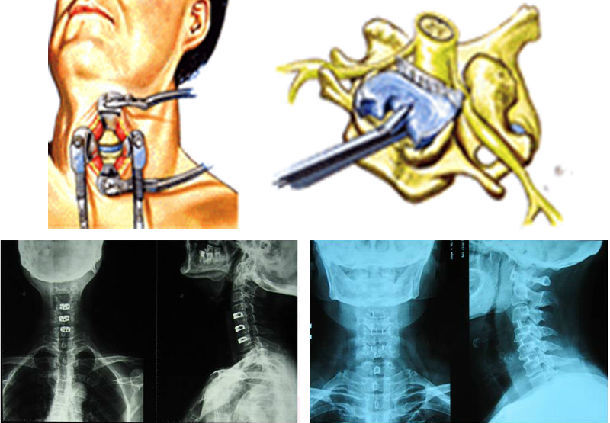

1 问: 颈椎压迫神经一定要手术吗 答: 不一定需要手术。中医的针灸、推拿、整脊加上自身锻炼(如练以宗第1到第7式)和服用中药。可以恢复。Apr 06, 16 · 开刀手术主要是针对颈椎病病情严重的患者或者保守、微创治疗无效的患者,往往作为最后的选择。 开刀手术存在创伤大、流血多、误伤其他组织等危险,也能导致术后脊椎不稳,易复发,影响患者以后的工作和生活。 相对而言,开刀手术的治疗费用几千到几May 30, 16 · 颈椎病症状主要是由于神经受压引起的,那么治疗关键就在于解除对神经的压迫。 开刀手术是其中的一种的方法但是该病属于退行性疾病,一般情况下建议先配合保守治疗。 对于正规保守治疗三个月以上,症状一点都没有缓解,严重影响生活和工作的情况下,结合查体考虑手术来治疗。 目前大多数患者选择药物方法来治疗,口服药物、打针、输液等方法,但是只能缓解

May 18, 12 · 全部症状:手指没力肌肉萎缩 发病时间及原因:12年5月 治疗情况:先想咨询一下还没治有后遗症吗?,Apr 12, 17 · 颈椎病症状主要是由于神经受压引起的,那么治疗关键就在于解除对神经的压迫。 开刀手术是其中的一种的方法但是该病属于退行性疾病,一般情况下建议先配合保守治疗。Sep 26, 18 · 由于颈椎疾病病变导致的压迫神经,从而引发的神经激惹和神经损伤症状,应该属于神经根型颈椎病,应该针对这种神经损伤症状做系统的治疗。 首先,要做颈椎的电动牵引,配合微波理疗、活血化瘀药物治疗,并且可以使用甘露醇脱水治疗,同时可以口服甲钴胺片剂做神经营养治疗。

May 22, 10 · 颈椎开刀后导致神经压迫使手脚不灵活78年了 有什么办法可以治疗吗 急急,由于开刀的费用是非常昂贵的和可能出现的后遗症。所以,没有去开刀。 再一次偶然的机会女儿通过朋友的介绍,尝试了这"冷敷贴",结果用不到两个疗程就解决这老人家90%的困扰。 适合用于: 肩膀颈椎,腰部,手脚酸麻胀痛绷紧! 欢迎询问: 微信号tuckkhorFeb 02, 21 · 颈椎病的治疗以非手术治疗为主,如针灸、推拿、针刀、松解、药物治疗等,其中最常用的是药物治疗,包括膏药贴、口服药物等。 颈椎椎间盘突出可以压迫神经根,引起一系列颈丛、臂丛的症状,这类患者治疗时可以选用射频、臭氧、等离子方法治疗。 症状严重的颈椎病患者,如椎管狭窄非